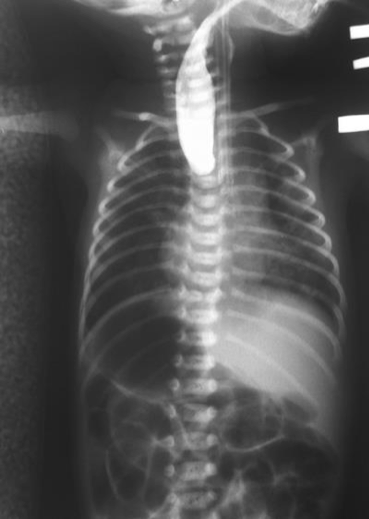

Esophageal Atresia

incomplete separation of the esophagus from the trachea

V.A.C.T.E.R.L. syndromes/associations

V = vertebral defects

A = anal atresia

C = cardiovascular defects

T/E = tracheoesphageal fistula

R = renal defects

L = upper limb defects

*syndrome = all defects; association = only some*